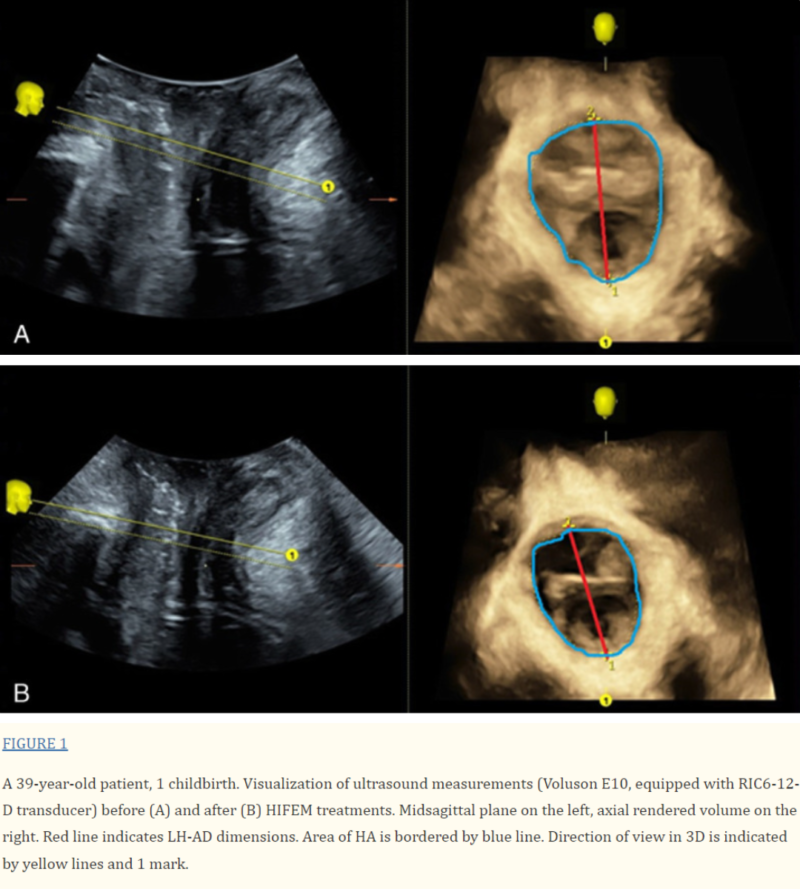

The 3D ultrasound images taken before and after HIFEM treatments are shown in Figure 1. It clearly shows improvements in the pelvic floor measurements, specifically in the LH-AD and HA parameters. The LH-AD thickness decreased by 2.6 mm, which is similar to the average reduction for all of group I (3.12 mm). Additionally, the HA measurement showed an even greater reduction of 1.83 cm², which is almost 0.5 cm² more than the group I average decrease of 1.38 cm².

Ultrasounds are a reliable way to examine the pelvic area. Since the pelvic floor is made up of complex structures, a 2D image might not show everything clearly, so we used 3D imaging for a more detailed view. This technology can detect pelvic floor weakness even before the patient notices symptoms, helping doctors start treatment early. The 3D scans allow us to measure specific areas of the pelvic floor and assess how well it’s functioning.